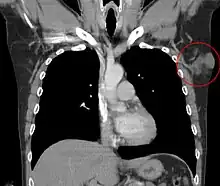

Distant hematogenous metastases are extremely rare.[35] Metastases to regional lymph nodes are rarer and are most likely in patients who have had multiple local recurrences after inadequate surgical resection.[36] Repeatedly recurring tumors have an increased risk for transformation into a more malignant form (DFSP-FS). The lungs are most frequently affected, but metastases to the brain,[37] bone,[38] and other soft tissues are reported.